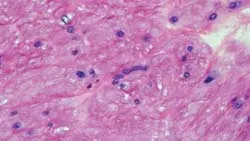

Leiomyoma (benign) and leiomyosarcoma (malignant) are composed mainly of smooth muscle (Figure 2) and occur in middle-aged to geriatric dogs with no evident sex predilection. Although there is no definitive breed predilection, poodles and Chihuahuas appear to be overrepresented.1

Figure 2. Leiomyoma has atypical spindloid cells that proliferate as broad interlacing fascicles, mimicking normal smooth muscle. (H&E stain, 40×)

Both tumor types are usually an incidental finding at necropsy. Typical gross appearance of leiomyoma is a semifirm to firm solid mass that is pale pink to tan.1

GI stromal tumors (GISTs), which cannot be distinguished from smooth muscle tumors with H&E staining, also have reportedly caused hypoglycemia, so additional testing is necessary to confirm smooth muscle differentiation. GISTs are believed to originate from interstitial cells (myofibroblasts), which are precursors to the pacemaker cells of the intestinal wall.1,4 Differentiation is possible with immunohistochemistry. GISTs will likely stain with S100, neuron-specific enolase, synaptophysin, or c-kit protein.1,4 In this case, immunohistochemistry revealed no uptake of c-kit staining, thus supporting the diagnosis of leiomyoma.